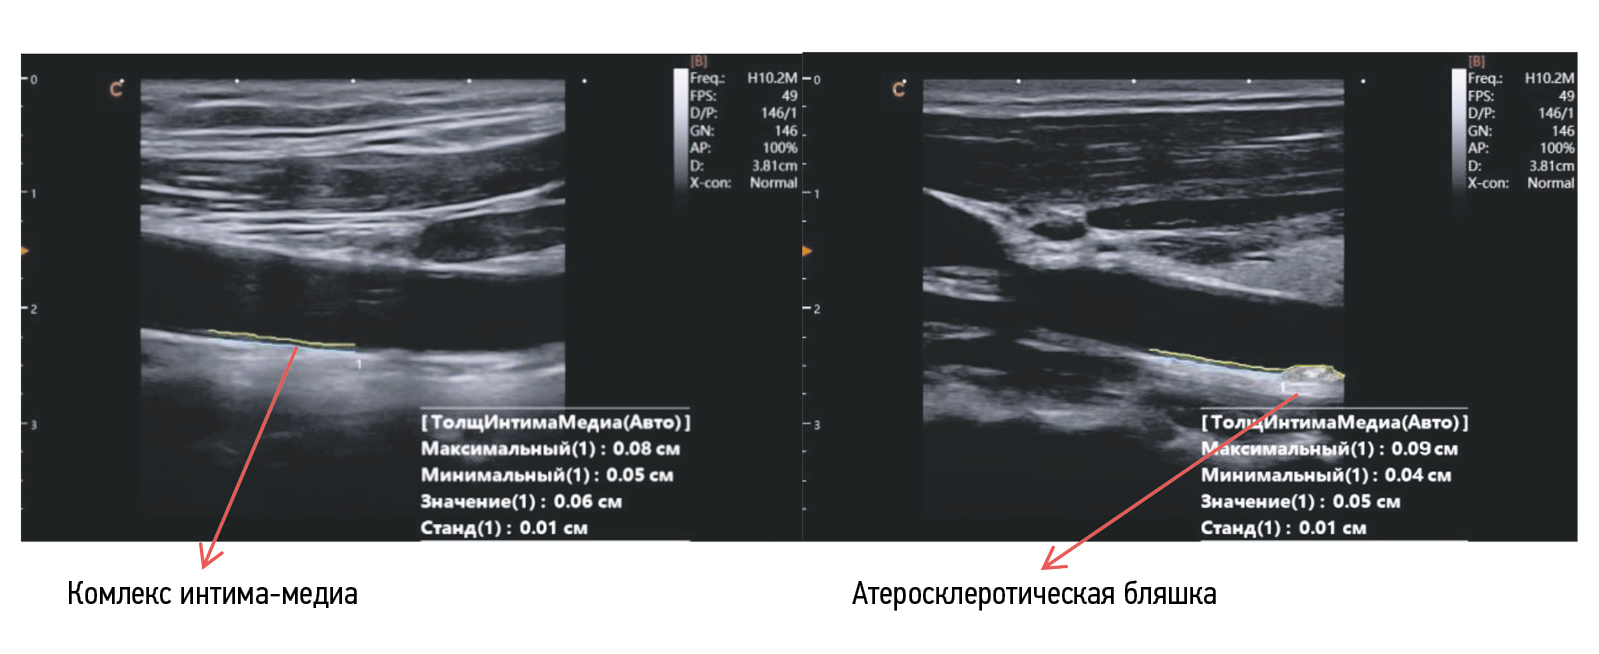

По результатам автоматического измерения ТКИМ ОСА на сонограммах в группах арктического и умеренного климатических поясов, наблюдалась определенная закономерность. Так, в умеренном климатическом поясе зависимость ТКИМ ОСА от продолжительности военной службы не имела достоверной значимости. В то же время у военнослужащих арктического климатического пояса в 1-й и 2-й группах ТКИМ была в пределах нормы, а у 11 (16 %) военнослужащих 3-й группы обнаружено увеличение максимальной величины ТКИМ более чем на 50 % от ее среднего значения, что указывает на наличие скрытой формы хронического прогрессирующего воспалительного заболевания стенки ОСА — субклинического атеросклероза (рис. 2).

Рис. 2. Сонограмма автоматического измерения ТКИМ ОСА аппаратом УЗД у военнослужащих без атеросклероза и страдающих субклиническим атеросклерозом, проходящих службу в арктическом климатическом поясе

Fig. 2. Sonogram of automatic measurement of the thickness of the intima–media complex of the common carotid artery using an ultrasound diagnostic apparatus in military personnel without atherosclerosis and suffering from subclinical atherosclerosis who were serving in the Arctic climatic belt

Факт субклинического атеросклероза выявляли на задней стенке (четкая визуализация на сонограммах) общей сонной артерии (ОСА) хотя бы по одной атеросклеротической бляшке, определяемой как увеличение максимальной величины ТКИМ более чем на 50 % от среднего значения ТКИМ ОСА. Подсчет ТКИМ производился автоматически на аппарате УЗД «Сhison Sonotouch 80» (Китай) с использованием ультразвукового датчика линейного формата с частотой до 7,5 МГц.

У военнослужащих со стажем службы более 10 лет в арктическом климатическом поясе на фоне обструктивного типа нарушения функции внешнего дыхания и гипоксемической гипоксии выявлено нарушение в системном и периферическом кровообращении. У них происходит ремоделирование стенки артериальных сосудов и артериол в виде повреждения эндотелия с развитием эндотелиальной дисфункции и атеросклероза. По нашему мнению, ведущим патогенетическим звеном эндотелиальной дисфункции артериальных сосудов является резистентность миоцитов к воздействию экспрессируемых сосудистым эндотелием факторов вазодилатации (NO). Чем больше стаж службы военнослужащих в условиях полярной гипоксии, тем вероятность развития эндотелиальной дисфункции выше. Так, у 11 (16 %) военнослужащих со стажем военной службы более 10 лет в арктическом поясе при УЗИ ОСА обнаружено увеличение ТКИМ более чем на 50 % от ее среднего значения, что указывает на наличие скрытой формы хронического прогрессирующего воспалительного заболевания стенки сосуда — субклинического атеросклероза.